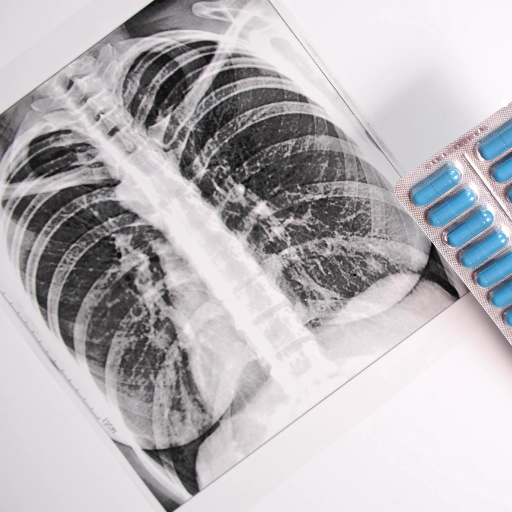

Pulmonology